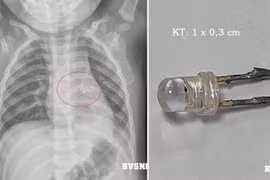

Nên thận trọng và thường xuyên nhắc nhở trẻ, chú ý khi trẻ tiếp xúc với những đồ dùng nhỏ, có cạnh sắc, nhọn có thể gây tổn thương thực quản, khí phế quản như: đầu bút, mảnh đồ chơi….